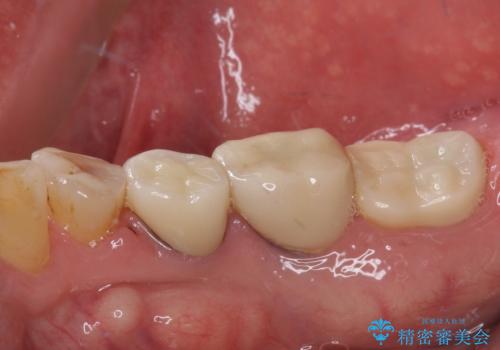

- 強い咬合力により表面のセラミックが剥がれ、裏打ちの金属が見えてしまっていることを気にして来院された患者様です。

仮歯に変えた後、咬合力に耐えることを目的に強化セラミッククラウンにて補綴することとしました。

歯肉が退縮したことで見えていた歯根もセラミッククラウンで覆うことができ、清掃性も改善されました。